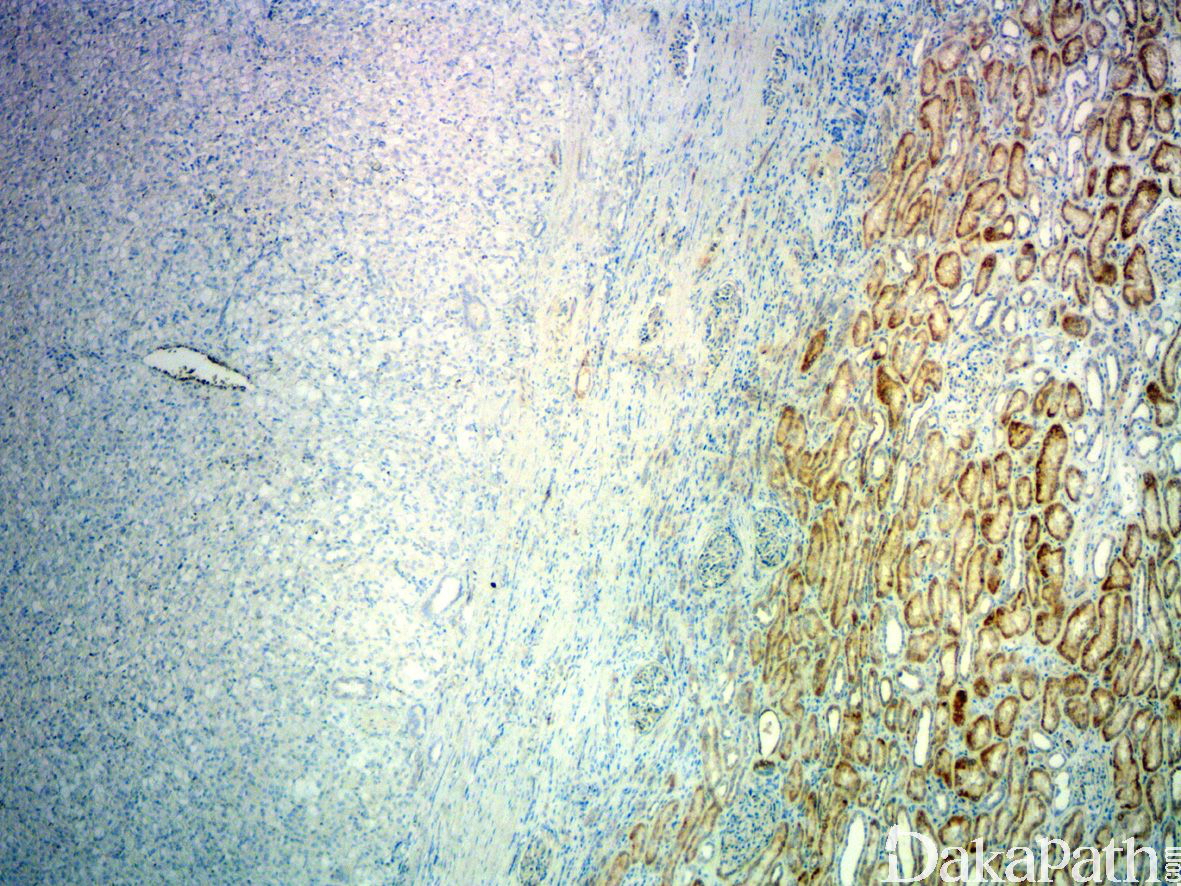

诊断 SDH-RCC 需要存在 SDHB 的免疫染色丢失,在判读 SDHB 免疫组化表达时需要与周围的正常组织作比较,只有周围组织对照阳性且肿瘤细胞完全阴性时才能判读为 SDHB 表达丢失。罕见的情况下,当 SDH-RCC 与 SDHA 基因突变相关时,肿瘤除了 SDHB 表达缺失之外,SDHA 免疫组化表达也缺失。SDH-RCC 弥漫表达 PAX-8 和肾特异性粘附蛋白,仅 30%表达广谱 CK,不表达 CK7,C-KIT, E-cadherin, 波形蛋白,CD10 等